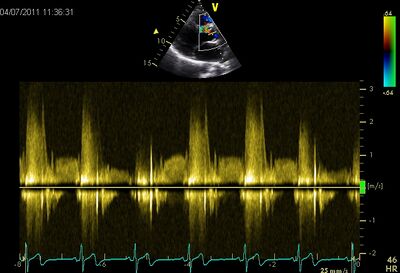

VSD09.jpg VSD10.jpg

Perimembraneus VSD PSAX Ao CW perimembraneus VSD PLAX